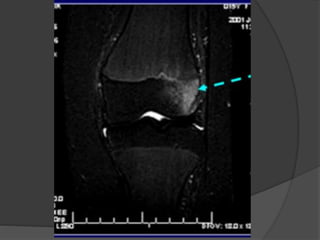

Osteonecrosis  Se instalacuanto el traumatismo produce daño vascular  Causas no traumáticas  Embolización arterial: Hb-patías, descompresión, embolia grasa pancreatitis  Vasculitis : LES  Presión intraósea elevada  Inhibición de la angiogenia (esteroides)  Tensión mecánica  Exposición a radiación